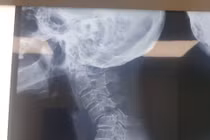

(khoahocdoisong.vn) - Đa phần bệnh nhân bị gãy trật cột sống cổ sẽ bị liệt hoặc tử vong. May mắn một bệnh nhân nữ 70 tuổi đã được phẫu thuật cứu sống không để lại di chứng sau 5 ngày bị gãy trật đốt sống cổ C4-C5 độ III.